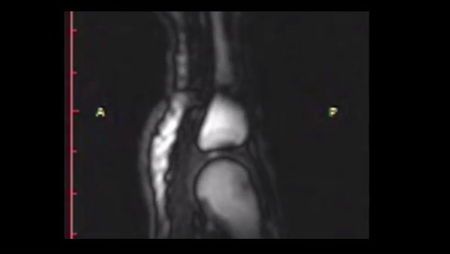

Perchè schioccano le dita – Molte persone prima di affrontare un compito difficile si scrocchiano le dita. Lo stesso nome indica un rumore, uno schiocco, che è tipico di questo gesto. Quando uniamo le nostre mani e tiriamo le dita si emette un suono caratteristico, di cui ora si è scoperta l’origine. Un team di ricercatori dell’università di Alberta, guidati dal professor Greg Kawchuk, ha scoperto perchè schioccano le dita. Il segreto di questo suono è un momentaneo spazio vuoto formato nel fluido sinoviale tra le ossa delle dita e delle nocche. Quando l’articolazione è allungata in modo eccessivo, si forma questo spazio vuoto nel gas, simile a un bolla, che produce il caratteristico rumore al momento dello scoppio. Dopo numerose ricerche gli scienziati hanno dunque compreso perchè schioccano le dita, una scoperta che servirà per nuovi studi sulle articolazioni. Secondo Greg Kawchuk la scoperta del perchè schioccano le dita potrà portare a in miglioramento nelle analisi delle ferite alla colonna vertebrale, ai problemi al ginocchi e altre difficoltà delle articolazioni, rilevando i problemi prima della loro comparsa. I ricercatori del team di Kawchuk sono riusciti a capire perché schioccano le dita grazie all’Imaging a risonanza magnetica visualizzato in modo estremamente rallentati. Come si vede nel video, è stato filmato anche un piccolo flash bianco prima che schiocchino le dita, che in futuro potrà essere analizzato con più precisione quando miglioreranno le tecnologie di ripresa e visualizzazione dell’Imaging a risonanza magnetica.

Photocredit: Screenshot di Youtube/RehabMedicineUofA